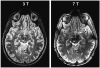

Methods: Using a 7-T MRI scanner combined with an array of acquisition schemes using multiple image contrasts, we obtained high-resolution images of human deep nuclei in healthy subjects.

Results: Superior image resolution and contrast obtained at 7 T in vivo using susceptibility-weighted imaging dramatically improved anatomic delineation of DBS targets and allowed the identification of internal architecture within these targets. A patient-specific, 3-dimensional model of each target area was generated on the basis of the acquired images.